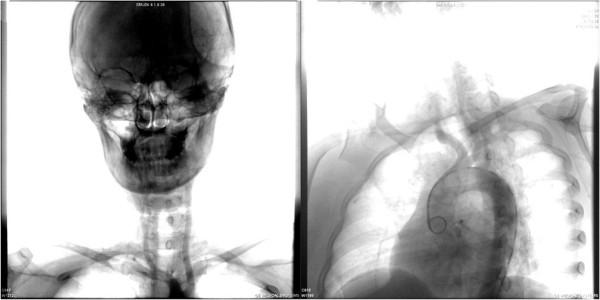

A 35-year-old Chinese woman presented to the Emergency Department with left hemiparesis, pain and numbness of her arms and weak radial pulses. Her laboratory results showed an elevated C-reactive protein and erythrocyte sedimentation rate, and subsequent digital subtraction angiography demonstrated narrowing and occlusion of the major branches of her aortic arch. We report the case of a patient with Takayasu arteritis presenting with a massive cerebral ischemic infarct and review the current literature on this topic.

一名35岁的中国女性因左侧偏瘫、手臂疼痛和麻木以及桡动脉搏动减弱就诊于急诊科。她的实验室检查结果显示C反应蛋白和红细胞沉降率升高,随后的数字减影血管造影显示其主动脉弓主要分支狭窄和闭塞。我们报告一例患有高安动脉炎并出现大面积脑缺血梗死的患者病例,并回顾关于该主题的当前文献。